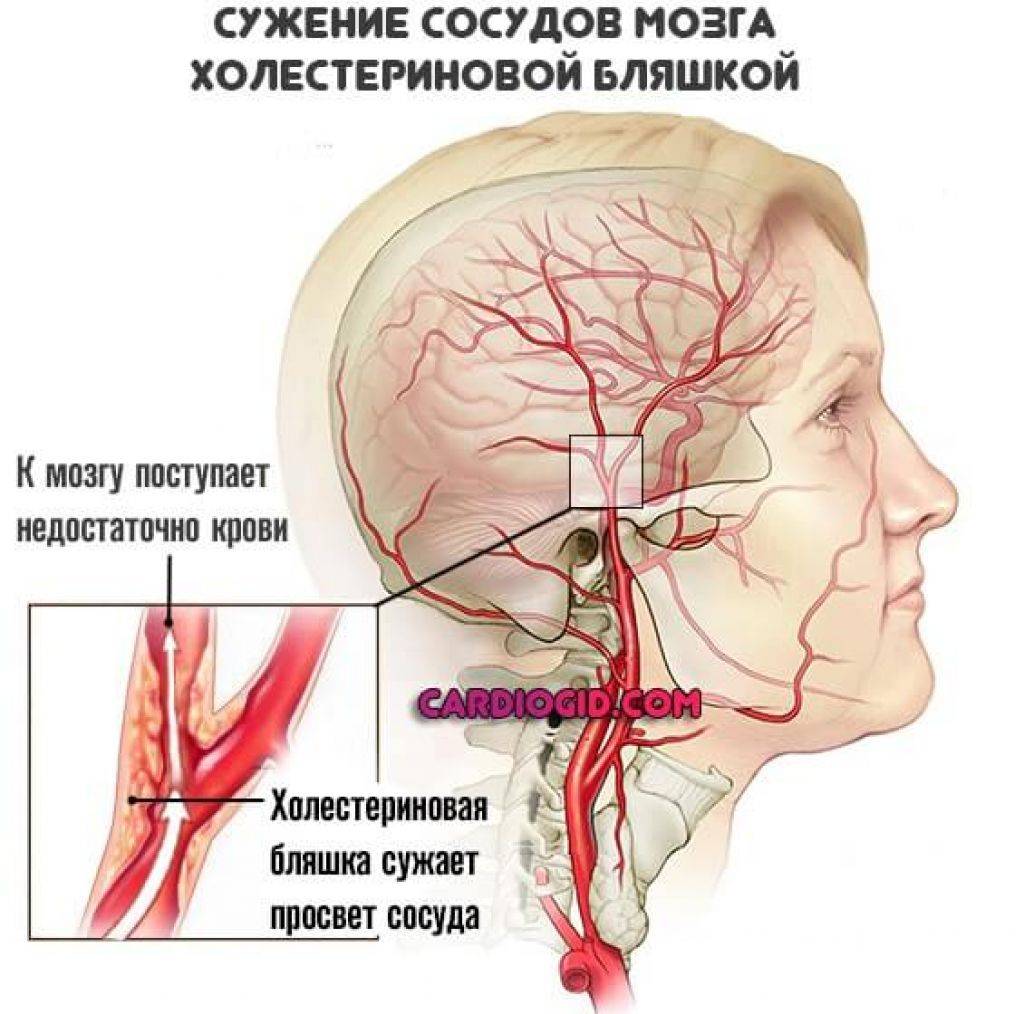

Хроническая ишемия головного мозга и лейкоареоз: симптомы и лечение